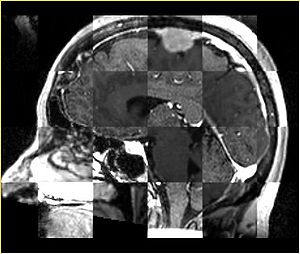

• Checkerboard appearance of unregistered images for the representative data of interest

• Case01